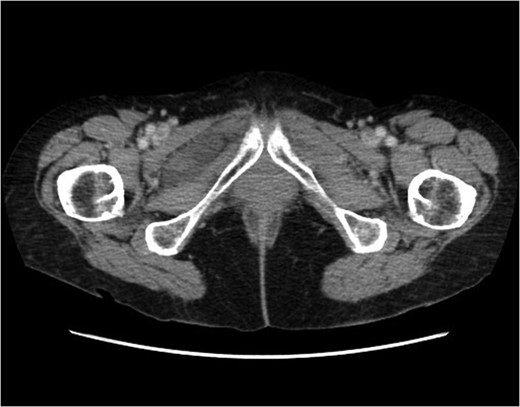

Coronal plane. The right obturator hernia is demonstrated. It contains small bowel loop. Proximal small bowel is mildly dilated. Right obturator hernia with features of incomplete small bowel obstruction.